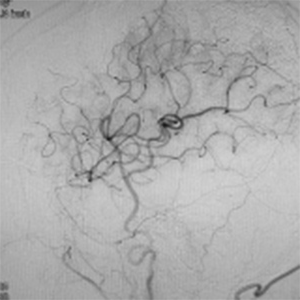

閉塞した脳血管

バイパス術で増加した脳血管